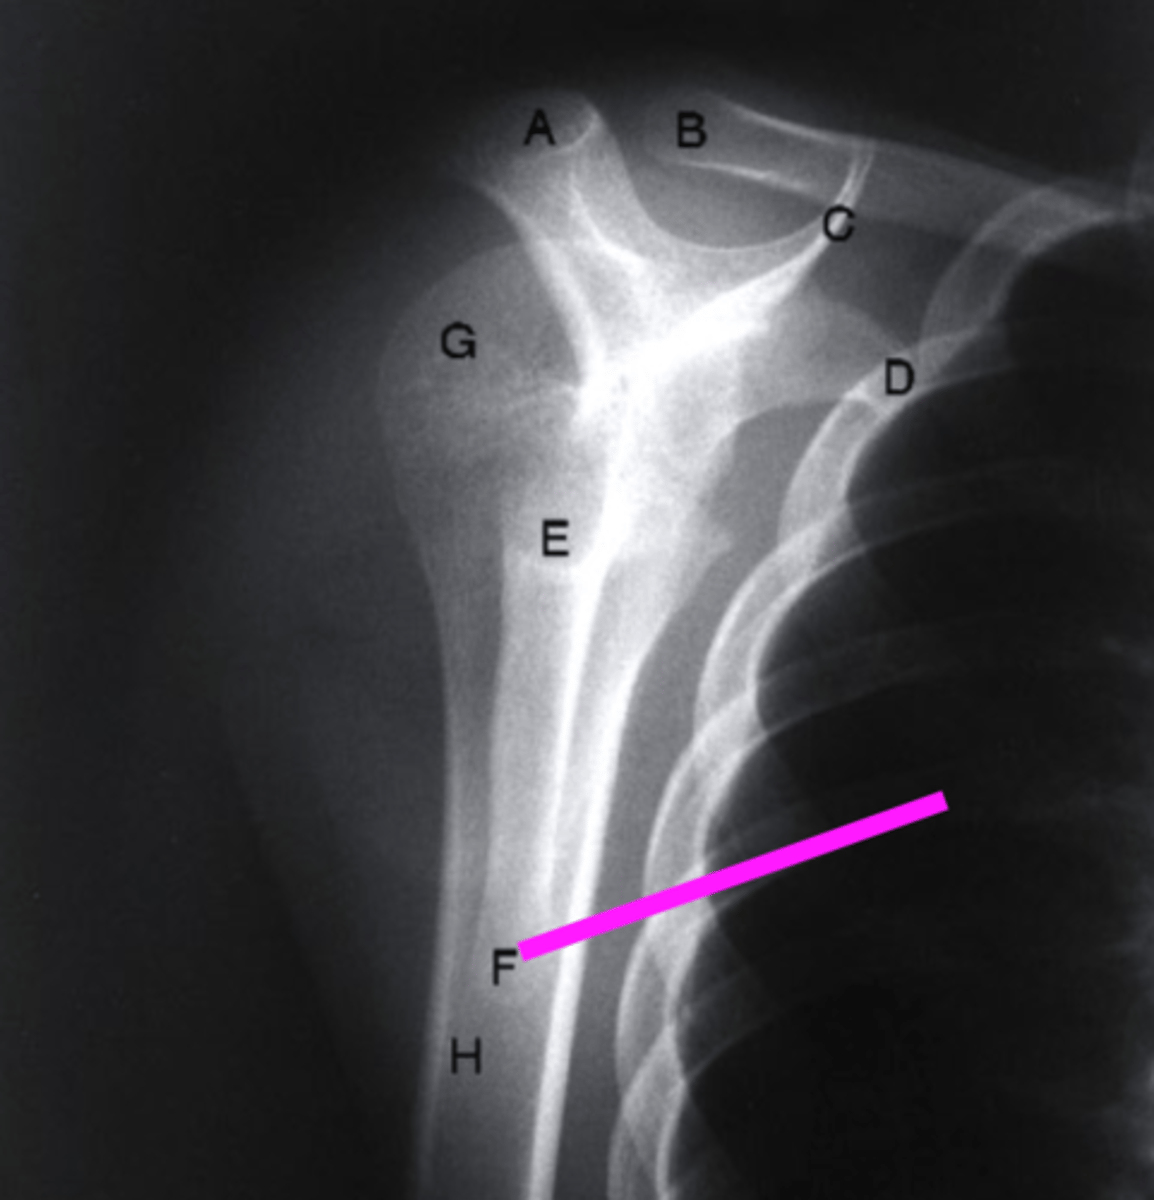

AP + IR

what view is this?

clavicle

what does the pink line point to?

spine of scapula

coracoid process

glenoid fossa of scapula

AC joint

acromion

Humeral Head

lesser tubercle